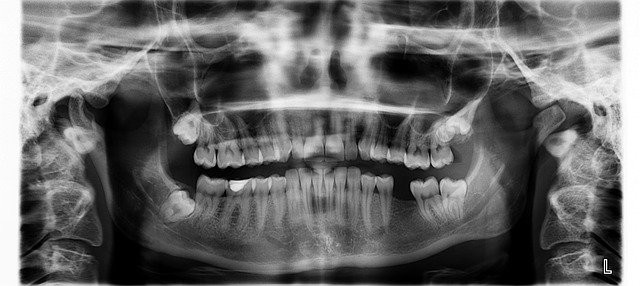

사랑니란 어금니 중에서도 제일 뒤쪽에 위치한 치아다.

어금니들 중에서 제일 끝인 세 번째에 있어 제3대구치라 불러도 된다.

이외에도 틀어져 나는 경우가 많아 발치를 꼭 해야 할 수 있다.

사랑니 발치 부작용으론 드라이소켓이 있다.매복사랑니란 잇몸 밑에서 자라는 사랑니다.

매복사랑니가 생기는 원인은 아직 정확하게 알려져 있지 않지만 인간이 진화하면서 아랫턱이 축소되면서 사랑니까지 완전하게 자라지 못한다는 의견이 많다.

매복사랑니는 잇몸의 아랫쪽에서 앞 치아를 밀어내 통증이 있을 수 있고 부기 및 염증을 유발하기 쉽다.